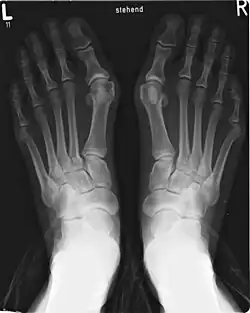

Um joanete é uma deformidade da Articulação metatarsofalângica que liga o dedo grande do pé. O dedo grande do pé, muitas vezes, se dobra em direção a outros dedos e a junta se torna vermelha e dolorosa. O início é gradual e as complicações podem incluir bursite ou artrite.[1]

A causa exata não é clara.[2] Os fatores propostos incluem o uso de sapatos excessivamente apertados, o histórico familiar e a artrite reumatóide. O diagnóstico baseia-se geralmente nos sintomas, com o apoio de raios-X. No caso do dedo mínimo, há uma situação semelhante, designada como bunionette.[1]

O desvio lateral pode ocorrer na articulação, formando o joanete clássico, com a proeminência óssea na base do hálux, ou entre dois ossos, formando o hálux valgo interbolangeano, ou interbolangico.